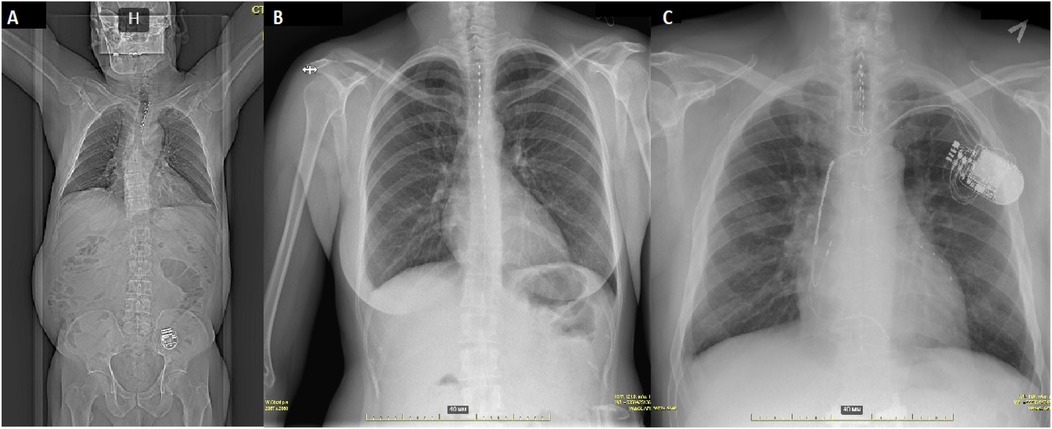

Background: Refractory angina pectoris represents a significant clinical challenge characterized by persistent chest pain despite maximally tolerated medical therapy and optimal revascularization attempts. This study evaluates the efficacy and safety of invasive spinal cord stimulation (SCS) in patients with refractory angina. Methods: Twenty-one patients underwent neurostimulation system implantation between 2022 and 2023 (mean age 62.8±7, 12 males) diagnosed with refractory angina. All patients received both chronic continuous stimulation and on-demand stimulation to alleviate anginal pain episodes. The primary endpoint was changes in the Seattle Angina Questionnaire (SAQ-19) scores. Secondary endpoints included changes in the Short Form Health Survey (SF-36), incidence of major adverse cardiovascular events, device-related complications, and nitrate use. Results: Eighteen patients completed the final follow-up. No statistically significant improvements were observed in any SAQ-19 domains. However, reductions in pain scores (41% vs. 53%, p=0.007) and improvements in mental health scores (61% vs 72%, p=0.021) and physical functionating (36 vs 52%, p = 0.017) were noted on the SF-36. Device extraction occurred in three cases (14%) - two due to pocket infection and one at the patient's request. Four lead repositioning procedures were performed (19%). Hospitalization rates significantly decreased over the one-year observation period, from 3.8 to 0.5 hospitalizations per patient (p=0.03). Recurrent acute coronary syndrome was noted in one patient, requiring additional coronary stentings. Notably, although no significant reduction in nitrate therapy was achieved, the treatment regimen prevented any new nitrate prescriptions during the study period. Conclusion: SCS did not significantly improve the primary endpoint of disease-specific quality of life (SAQ-19). However, treatment was associated with secondary benefits, including improvements in physical functionating, pain and mental health (SF-36) and a significant reduction in hospitalization rates. Complication rates were significant.